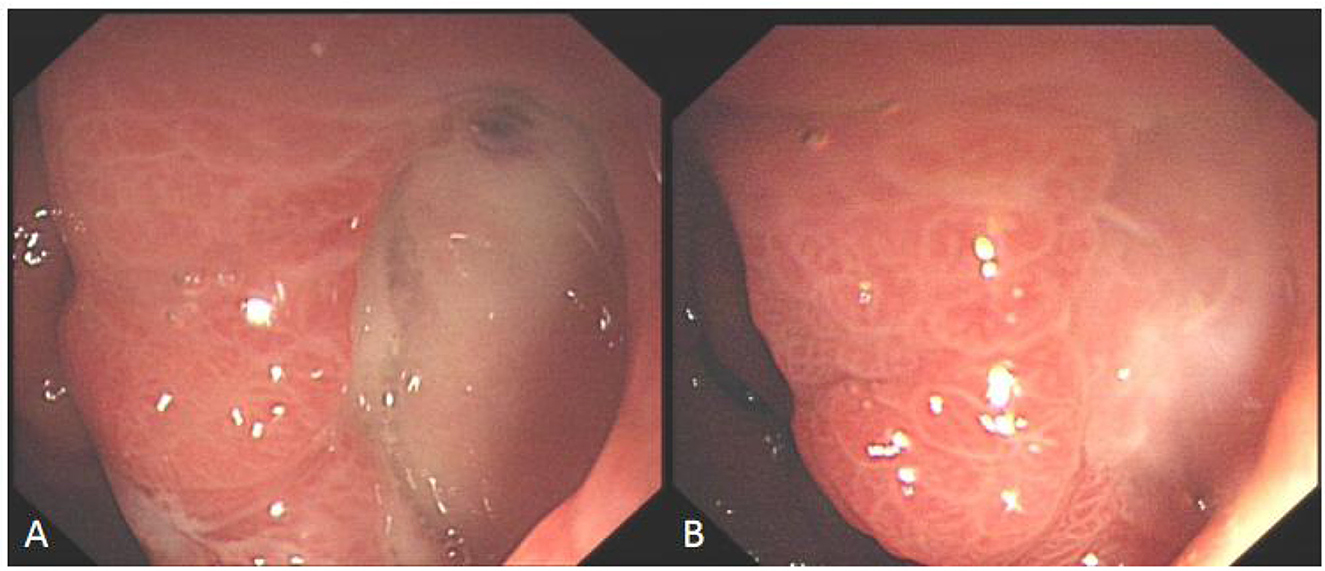

Some cases of hyperbaric oxygen therapy for refractory peptic ulcer disease (Figures 46).

Figure 5

Panels A and B show endoscopic images of the gastric antrum. Panel A displays a prominent fold with visible vascularity, while Panel B shows mucosal changes with a glistening appearance.

Figure 5. Comparison before and after hyperbaric oxygen treatment of ulcer on the posterior wall of gastric antrum. (A) Intractable ulceration of the posterior wall of the gastric antrum, approximately 1.8 cm × 2.5 cm, the broken ends of blood vessels are visible on the surface. (B) After 2 weeks of hyperbaric oxygen treatment, the ulcer was about 6 mm × 12 mm in size, with granulation tissue growing on the surface and no broken ends of blood vessels.